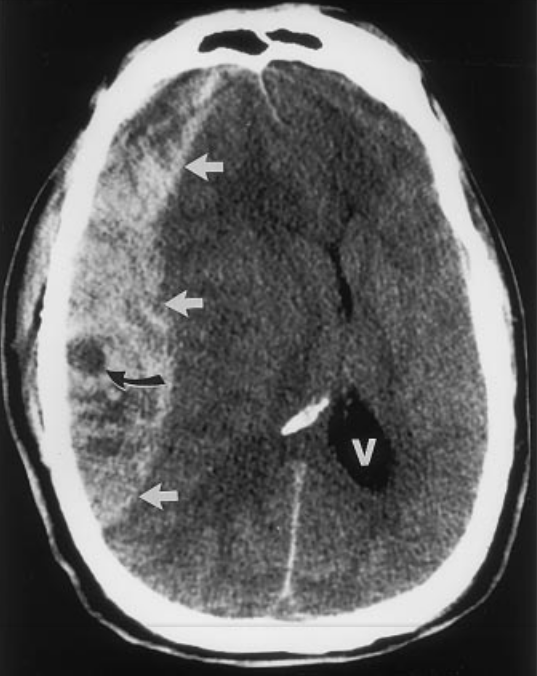

Swirl Sign CT

Axiale CT Bildgebung des Schädels einer hyperakuten Blutung (weiße Pfeile) mit Swirl Sign (schwarzer Pfeil).